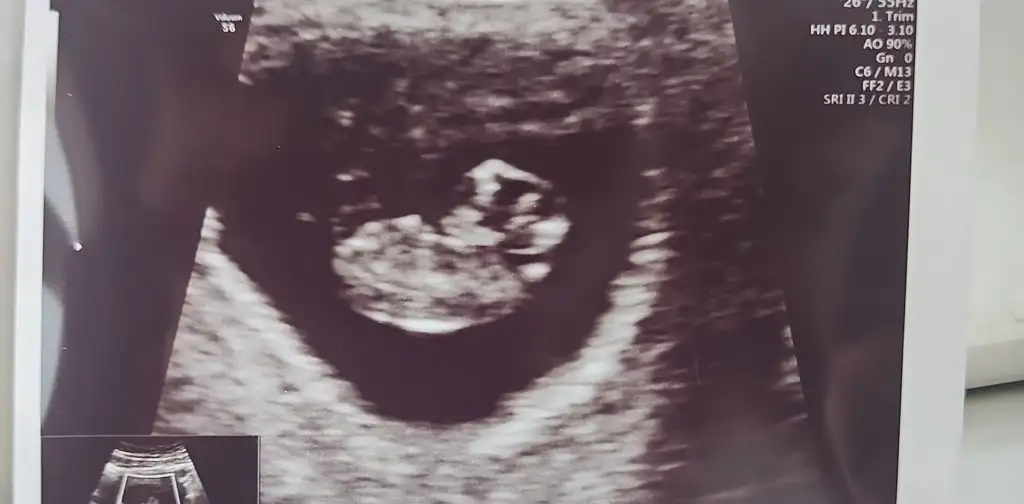

Canim banada tahminde bulunabilirmisin rica etsem.12+4 vaginal.Selam Kızlarbir çok kişi gruplardan beni bilir. Yine yetiştim imdatlara

Benimkinede bakarmısınız rica etsem 9+5Selam Kızlarbir çok kişi gruplardan beni bilir. Yine yetiştim imdatlara

Plesanta sağ da erkek canımmerhabalar ilk bebişimiz merakla bekliyoruz6. haftanın içindeyken gitmiştik,karından ultrason tahmininizi çok merak ediyorum